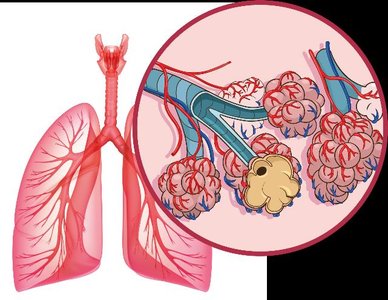

Example: The lungs' thin walls and alveoli increase surface area for efficient gas exchange.

Respiratory System: Lungs, trachea – gas exchange.